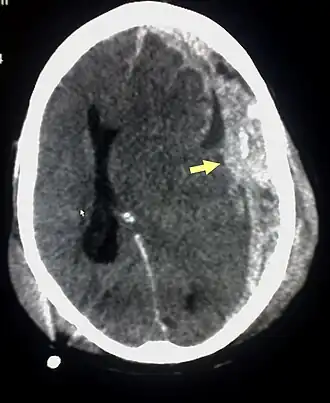

Lesões características associadas com SBS incluem hemorragia retiniana, fraturas múltiplas dos ossos longos e hematomas subdurais (hemorragia cerebral).[5] Estes sinais foram estabelecidos com os anos como os sinais aceitos e reconhecidos de maus-tratos infantis e síndrome do bebê sacudido. Os profissionais da área médica suspeitam desta patologia quando o recém-nascido, lactente jovem ou criança apresenta hemorragia retiniana, fraturas, lesões de tecidos moles ou hematoma subdural, que não podem ser explicados por trauma acidental ou outras afecções médicas.[6]

A maior parte dos casos ocorrem em lactentes, os quais têm uma desproporção excessiva entre o grande tamanho da cabeça em relação ao restante do corpo, e um tônus muscular insuficiente nos músculos do pescoço, que não lhes permite suportar o peso e as oscilações da cabeça. Por suas fragilidades inerentes a idade, após sacudida, ocorre hipóxia pela dificuldade respiratória, provocando alterações do centro respiratório troncoencefálico, muitas vezes formando edema cerebral e hemorragias subdurais, com pequenas contusões parenquimatosas e ou múltiplas hemorragias axiais adicionais.[7]

Resultados adicionados de SBS são lesão axonal difusa, privação de oxigênio e edema cerebral,[11] o qual pode elevar a pressão dentro do crânio e danificar tecidos cerebrais delicados. As vítimas de SBS podem mostrar irritabilidade, crescimento insuficiente, alterações em padrões de alimentação, letargia, vômitos, convulsões, protuberância ou tensão nas fontanelas (os pontos macios na cabeça de um bebê), aumento do tamanho da cabeça, respiração alterada, e pupilas dilatadas.[7][12][13]

O SBS pode ser mal diagnosticado ou subdiagnosticado, e os cuidadores podem mentir ou não ser conscientes dos mecanismos da lesão.[15] Normalmente, não há sinais visíveis da afecção.[15] O exame do oftalmologista frequentemente é uma condição essencial para o diagnóstico da síndrome do bebê sacudido, pois formas particulares de derrame ocular são muito características.[30] -->[31] Imagens por ressonância magnética também podem mostrar hemorragia retiniana;[32] Pontualmente isto pode resultar útil sem um exame do oftalmologista demora-se ou não está disponível. Afeições que devem ser descartadas incluem hidrocefalia, síndrome de morte súbita do lactente (SMSL ou SMLS, em inglês), transtorno convulsivo, e doenças infecciosas ou congênitas como meningite e transtornos metabólicos.[16][33] Empregam-se tomografia axial computadorizada (exploração por TAC) e imagens por ressonância magnética para diagnosticar a afeição.[15] Afeições que podem acompanhar SBS incluem fraturas ósseas, lesão das vértebras cervicais (no pescoço), hemorragia retiniana, hemorragia cerebral ou atrofia, hidrocefalia, e papiledema (inchaço do disco óptico).[11]

O tratamento envolve monitorizar a pressão intracraniana (a pressão dentro do crânio), drenar o fluido desde os ventrículos cerebrais, e, se está presente um hematoma intracraniano, drenar o sangue acumulado.[11]